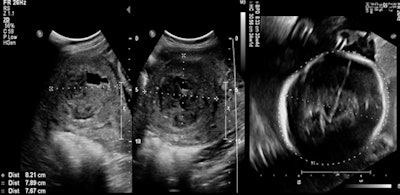

In this study, most women opted for UFE as a fertility treatment after failure of myomectomy or in vitro fertilization, or because hysterectomy was the only suggested option. Of the 210 patients who received UFE treatment, 35 women younger than the age of 40 wanted to conceive and had been unable.

In a retrospective chart review of patients younger than the age of 40 (35 patients) who wished to spare their fertility and underwent UFE from 2011 to 2016, 18 patients reported 23 pregnancies, of which five were miscarriages. Two more pregnancies were complicated by premature labor. Of the 23 pregnancies, 16 were normal full-term pregnancies, 15 women had become pregnant once, and four had become pregnant twice.